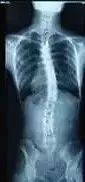

随着年龄的增长,脊椎侧弯可能会发生不可预测的恶性发展,危及生命。